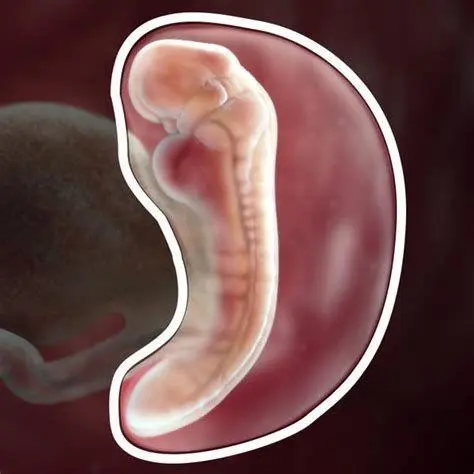

Estimasi Perkembangan dan Gejala pada Minggu Kelima

| Ukuran Janin | Sebesar biji wijen atau sekitar 2-3 milimeter. |

| Organ Utama | Mulai terbentuknya tabung saraf (bakal otak dan sumsum tulang belakang). |

Meskipun ukuran janin masih sangat kecil, jantung janin sebenarnya sudah mulai berdetak secara primitif pada tahap ini, meskipun mungkin belum bisa terdengar jelas melalui alat Doppler biasa. Pemeriksaan melalui USG Transvaginal biasanya sudah bisa memperlihatkan kantung kehamilan (gestational sac) di dalam rahim.